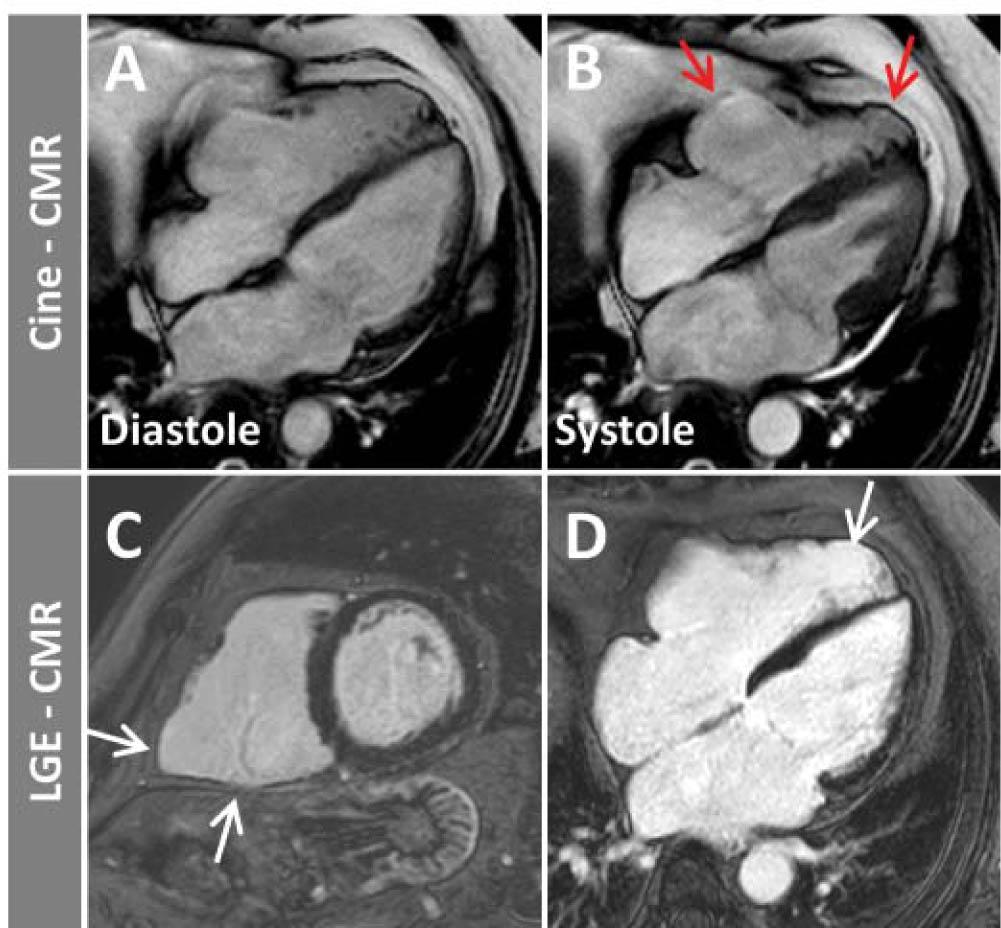

Figure 6

Cine images at end-diastole (A) and end-systole (B) as well as LGE images in basal short-axis (C) and four-chamber view (D) in a patient with arrhythmogenic RV cardiomyopathy. A dilated RV with dys-kinetic basal and apical lateral wall (B, red arrows) and corresponding fibrotic changes (LGE) in the basal inferior/lateral and apical lateral RV walls (C, D, white arrows) can be seen.